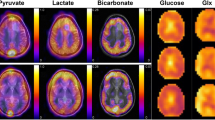

- MRS imaging

(MRSI). Applies magnetic resonance spectroscopy (MRS) in a spatially resolved manner, thereby providing metabolite concentrations in tissue in two or three spatial dimensions and allowing for the display of metabolic maps throughout the tissue.